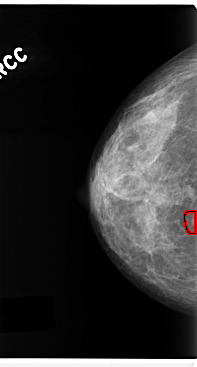

FILE: C_0212_1.RIGHT_CC.OVERLAY

TOTAL_ABNORMALITIES 1

ABNORMALITY 1

LESION_TYPE MASS SHAPE ROUND MARGINS CIRCUMSCRIBED

ASSESSMENT 4

SUBTLETY 5

PATHOLOGY MALIGNANT

TOTAL_OUTLINES 1

BOUNDARY